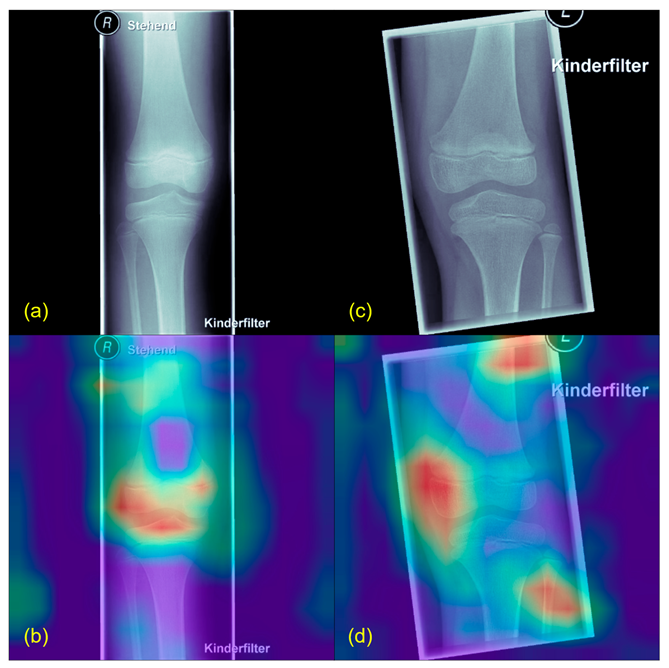

- Selvaraju, R.R.; Cogswell, M.; Das, A.; Vedantam, R.; Parikh, D.; Batra, D. Grad-CAM: Visual Explanations from Deep Networks via Gradient-Based Localization. Int. J. Comput. Vis. 2020, 128, 336–359. [Google Scholar] [CrossRef]